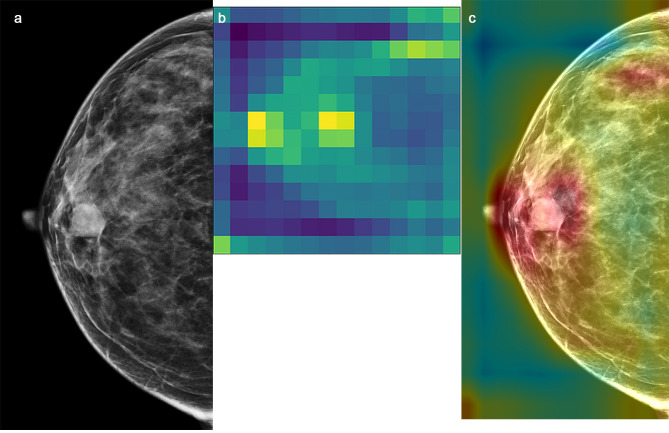

We fine-tuned a total of 11 layers, they were Mixed 0 ~ Mixed 10 layers, activated parameters corresponding to these layers are from 6 to 536 to 21 802 784. We sought to improve the performance of the Inception V3 model by devising 11 preset fine-tuning strategies. The parameters of the neural network were activated and participated in the model training process, whereas the parameters of the layers that were kept frozen were not involved in training the model (Fig. 2). We selected the parameter convergence and generalization capacity as the primary outcome measures for the DTL models. A visualization of the activation heatmap in the DTL model is shown in Fig. 3. Activation heatmap were made as described in reference [15].

Fig. 3.

Class activation heatmap for a malignant lesion. a: input mammographic image; the white arrow shows a benign breast lesion. b: Heatmap of (a)c: Fusion image of a and (b) The large intensity of activation in the breast lesion reinforcement region is evident from the heatmap, which may reflect the difference between benign and malignant breast lesions identified by the convolutional neural network. The lesion was pathologically confirmed as a fibroadenoma